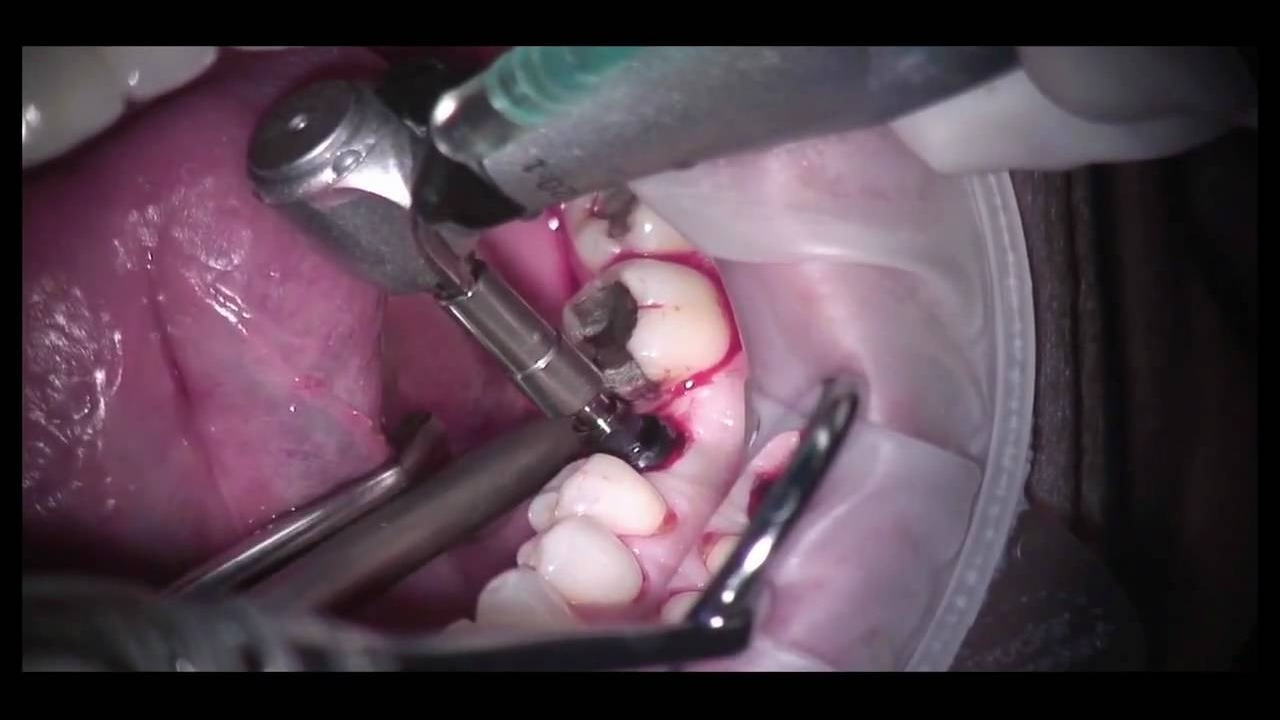

A dental implant is a permanent solution for replacing missing teeth by placing a titanium post into the jawbone, which acts as an artificial tooth root. Once the implant integrates with the bone, a crown, bridge, or denture is attached to restore normal function and appearance. Dental implants provide a natural look, strong chewing ability, and help preserve jawbone health, making them a reliable and long-lasting tooth replacement option.